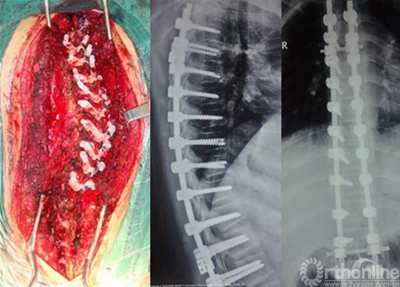

通过Geomagic studio12参考最佳进钉点所在的位置,提取椎体后部解剖形态,设计与椎板后部解剖形态一致的反向模板(图2),与椎弓根植钉通道拟合为一体,形成带有定位定向管道的数字化导航模板。在三维重建椎体模型上即可以进行虚拟植钉手术操作。再通过光固化成型技术(SLA)生成实模板体即可以辅助术中应用。在临床应用时可以确保每一枚螺钉正确的置入位置和方向(图3),真正体现了颈椎椎弓根螺钉置入的个体化原则。我们的临床应用范围已经包括了从上颈椎、胸腰椎到脊柱侧弯矫形等多个方面。

临床研究发现,每个导航模板都和相应椎体后部骨性解剖结构十分贴合,所有椎弓根螺钉置入较为满意。术后CT扫描发现椎弓根螺钉完全位于椎弓根内,进钉点准确、进钉角度恰当,螺钉长度及直径合适,无穿破椎弓根皮质及椎体前方的螺钉,患者无周围组织损伤症状。个体化的脊柱椎弓根导航模板对于手术医师只要将模板和暴露的椎板相贴合, 就可以进行钉道准备, 并不依赖于个人经验。模板的制作是个体化的制作, 可采用定制的方式, 因此临床上有应用方便,为颈椎椎弓根的定位提供了一种全新的方法。(如图4、图5)。

图4 术后X线及CT影像

图5 脊柱侧弯矫形术椎弓根导航模板的临床应用及术后X线影像